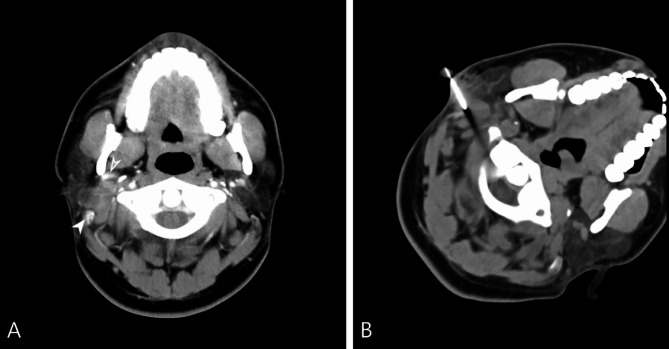

目的:舌骨上深部头颈部病变的病理诊断是重要的,组织取样需要平衡最小的侵入性和准确性。本研究的目的是评估ct引导下核心针活检(CNB)对舌骨上深部头颈部病变的诊断准确性和诊断失败相关因素。方法:回顾性分析204例ct引导下CNB患者的临床资料。ct引导下CNB采用18g同轴活检针进行病理诊断。病变诊断的准确性通过活检结果与手术标本的比较或根据治疗效果和6个月以上的临床随访来计算。通过卡方检验和程序特征和病变特征的logistic回归来确定与活检失败相关的因素。结果:所有204例标本均可用于组织学诊断,未发生立即或延迟的严重并发症。诊断敏感性为89.2%(141/158),特异性为97.8%(45/46),总体准确率为91.2%(186/204)。病变边界不清或术前诊断成像是诊断失败的潜在因素。结论:ct引导下的CNB是原发性舌骨上深部头颈部病变及颅底病变的有效组织诊断方法。值得注意的是,边缘不明确的病变和不理想的术前成像是导致诊断失败的潜在因素。具体来说,对于边界不清的病变,病变的范围难以划定,建议术前使用磁共振成像进行评估,以提高病变边缘的清晰度,从而有可能提高诊断的准确性。

Purpose: Pathological diagnosis is important for the treatment of deep suprahyoid head and neck lesions, and tissue sampling needs to balance minimal invasiveness and accuracy. The purpose of this study was to evaluate diagnostic accuracy and factors associated with diagnostic failure of core needle biopsy (CNB) with CT-guided in deep suprahyoid head and neck lesions.

Methods: The records of 204 patients who underwent CT-guided CNB were retrospectively reviewed. CT-guided CNB was conducted for pathological diagnosis with the use of 18-G coaxial biopsy needles. Diagnostic accuracy for the diagnosis of lesions were calculated by comparing the biopsy results with the operative specimen or based on treatment response and clinical follow-up more than 6 months. Factors associated with biopsy failure was identified by chi-square test and logistics regression of procedure characteristics and lesion features.

Result: All 204 specimens were deemed adequate for histological diagnosis, with no immediate or delayed severe complications encountered. The diagnostic performance showed a sensitivity of 89.2% (141/158), specificity of 97.8% (45/46), and overall accuracy of 91.2% (186/204). Respectively, lesions with poorly defined margins or pre-procedural diagnostic imaging were the potential factor for diagnostic failure.

Conclusion: CNB with CT-guidance is an effective procedure for tissue diagnosis of patient with primary deep suprahyoid head and neck lesions and skull base lesions. Notably, lesions with poorly defined margins and suboptimal pre-procedural imaging emerged as potential factors contributing to diagnostic failure. Specifically, for lesions with indistinct boundaries-wherein the extent of the lesion is difficult to delineate-pre-procedural assessment using magnetic resonance imaging is recommended to enhance the clarity of lesion margins, thereby potentially improving diagnostic accuracy.